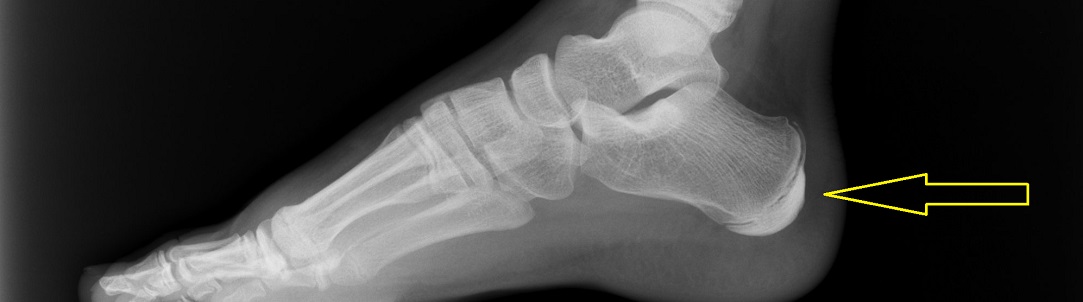

DIAGNOSTIKA

Při podezření na Severovu chorobu se zdravotníci zpravidla ptají na fyzické aktivity dítěte a provedou vyšetření zvláště zaměřené na patu.

Obvykle není nutné žádné další speciální vyšetření.

Ačkoli Severovu chorobu nelze na rentgenu vidět, někdy je vhodné RTG vyšetření provést, aby se vyloučily další možné problémy.